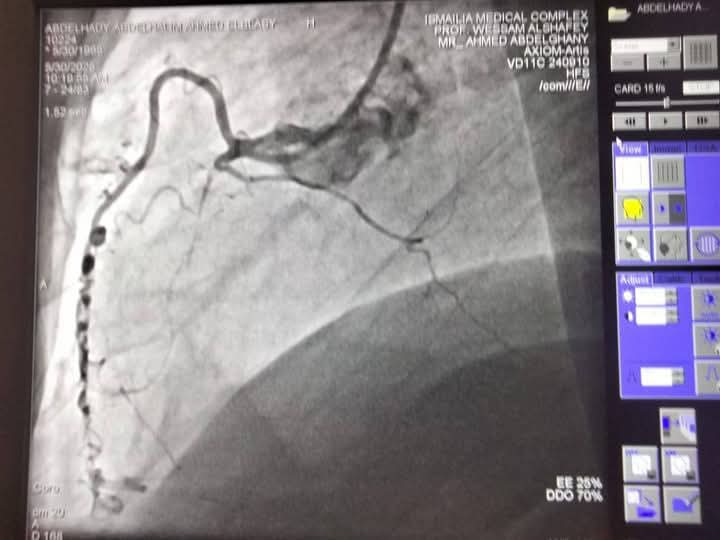

تمكن فريق قسطرة القلب في مجمع الإسماعيلية الطبي من إنهاء معاناة حالتين متوسط عمرهما 60 عامًا، كانتا تعانيان من أعراض متكررة لأزمات قلبية، بعد إجراء قسـطرة تشخيصية.

الحالتان كانتا تعانيان من انسداد في الشريان التاجي

وتبين وجود انسداد كلي مزمن في الشريان التاجي CTO-RCA، مما استدعى التدخل العاجل نظرًا لتعقيد وخطورة الحالات، وتحت إشراف خبير قسطرة الشرايين التاجية المعقدة بمجمع الإسماعيلية الطبي، وهما الأستاذ الدكتور وسام الدين الشافعي، تم إجراء قسطرة علاجية ناجحة لكلا الحالتين، حيث تم استخدام تقنيات حديثة تشمل توسيع الشرايين بالبالونات الدوائية وتركيب دعامتين دوائيتين للحالة الأولى، وثلاث دعامات للحالة الثانية.